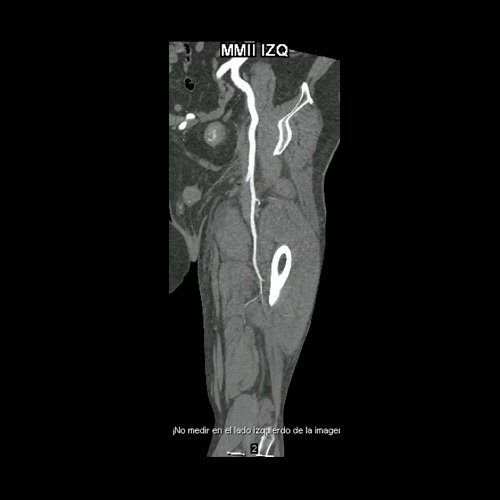

• AngioTAC de miembros inferiores (Día 2): Ateromatosis parietal calcificada parcheada en todo el territorio aorto-ilíaco-femoral bilateral. LADO DERECHO: Arteria ilíaca interna: de calibre y trayecto conservado, permeable. Arterias ilíaca externa y femoral común: de calibre y trayecto conservados, permeables. Arterias circunfleja ilíaca superficial y epigástrica superficial: de calibre y trayecto conservados, permeables. Arteria femoral superficial: de calibre y trayecto conservado, permeable. Arteria femoral profunda: de calibre y trayecto conservado, permeable. Arterias circunflejas femoral medial y lateral: de calibre y trayecto conservados, permeables. Arteria poplítea: de calibre y trayecto conservado, permeable. Arteria tibial anterior: de calibre y trayecto conservado, permeable. Arteria tibial posterior: de calibre y trayecto conservado, permeable. Vena ilíaca primitiva: 13 mm, vena ilíaca externa 11 mm, vena ilíaca interna 7 mm. LADO IZQUIERDO: En esta ocasión, en fase angiográfica se observa de calibre y opacificación conservada de las arterias femoral superficial y profunda, poplítea y de sus ramas musculares en muslo y pierna. En fase venosa se evidencia un defecto de relleno endoluminal de la vena primitiva izquierda que impresiona extenderse actualmente a la vena iliaca externa, a la vena femoral superficial y poplítea, hasta nivel del hueco homonimo, las cuales se visualizan aumentadas de calibre con respecto a sus contralaterales, en relación a trombosis venosa profunda. Se sugiere cotejar con ecodoppler de miembros inferiores. No se identifica compromiso de la porción visualizada de la vena cava inferior ni del sistema venoso ilíaco contralateral. Se visualiza dispositivo vascular en VCI (filtro VCI), infrayacente a las venas renales. Presenta aumento del diámetro del muslo izquierdo con respecto a su contralateral, asociado a edema de los tejidos blandos superficiales. Reticulación de la grasa de la región inguinal a predominio izquierdo con algunas burbujas aéreas. Se observa inmediatamente infrayacente a los antes mencionado, un área hiperdensa que realza en fase venosa, con centro hipodenso, que mide 2.2 cm x 1.4 cm, ya visualizado en tomografía previa. Cambios artrodegenerativos coxo-femorales y tricompartimentales en la rodilla. Signos de entesopatía cuadricipital distal. No se observan alteraciones a nivel del fémur ni de las porciones visualizadas de la tibia y el peroné. Arteria ilíaca interna: de calibre y trayecto conservado, permeable. Arterias ilíaca externa y femoral común: de calibre y trayecto conservados, permeables. Arterias circunfleja ilíaca superficial y epigástrica superficial: de calibre y trayecto conservados, permeables. Arteria femoral superficial: de calibre y trayecto conservado, permeable. Arteria femoral profunda: de calibre y trayecto conservado, permeable. Arterias circunflejas femoral medial y lateral: de calibre y trayecto conservados, permeables. Arteria poplítea, tibial anterior y tibial posterior: de calibre disminuido con respecto a su contralateral, permeables. Vena ilíaca primitiva: 14 mm, vena ilíaca externa 17 mm, vena ilíaca interna 9 mm. Calcificaciones en conducto inguinal bilateral. Hidrocele bilateral.

Angio TAC de miembros inferiores (Día 2)